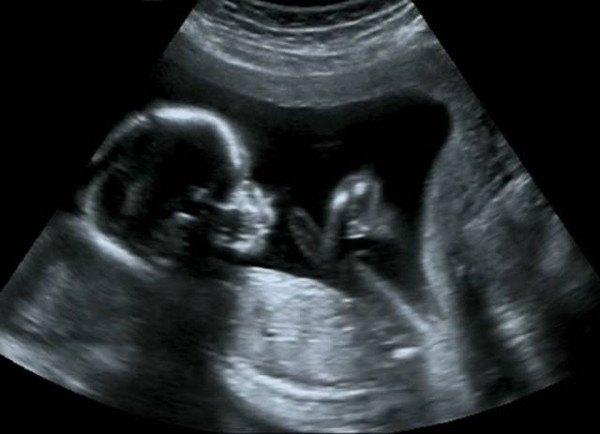

在产前检查的项目中,超声波是一种非侵入性的检查,可对胎儿的身体做检查,堪称妇产科医师的第三只眼。超声波不仅用于产前检查,举凡心脏科、内分泌科、消化科等临床检查,也常使用超音波做鉴别检查的工具。

虽然说产科超声波可以看出大部分胎儿的生长状况和异常问题,然而,现行台湾健保只提供一次免费的level I超声波检查的给付,检查内容主要是测量胎儿大小、羊水量和胎盘为置,检查时间在怀孕20周左右,千万不可与高层次超声波混为一谈。此外,孕妈咪有权决定是否接受超声波检查,即使做检查,也有权拒绝某些检查结果,请在检查前主动告知医师。反之,若是怀孕期间有任何的身体不适或胎儿有特殊状况,可以和医师讨论检查的频率与次数。

其实,针对不同的怀孕周数,超声波各有不同的检查重点,整个怀孕期间只检查一次略嫌不足。江其鑫医师指出,依据不同的孕期阶段,超声波检查的重点各有不同,简单归纳如下:

12周之后胎儿的四肢正在慢慢的发育中,之后也会逐渐发展成人形;

14~16周之后可以看到胎儿大小、四肢、羊水量、胎儿性别等,但医师不会主动告知胎儿性别;

到了怀孕20周,则是胎儿异常筛检的重要时间,检查重点有胎儿头围、双顶径、五官结构(是否有兔唇)、心脏四腔室、腹围、腹腔、是否有胃泡(表示有吞咽功能)、股骨长、胎盘、羊水量等;